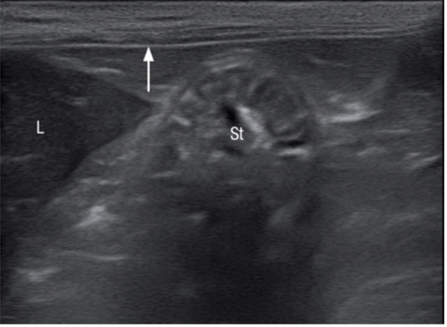

腹膜壁层在近场上呈现一条高回声亮线(图1)。器官表面的腹壁脏层又称为浆膜层,包裹在肠道外壁,胃的外壁,膀胱的外壁,脾脏和肝脏的外壁,也呈高回声的亮线(图2)。腹膜结缔组织连接腹腔各个器官,有3个双层腹膜结构,分布是网膜,肠系膜,韧带(图3)猫的镰状韧带位于肝的腹侧被脂肪组织所包裹,相较于肝脏实质的回声镰状韧带可呈无回声或低回声,偶尔呈高回声,它的质地更加粗糙些(图4)。肝脏包膜的高回声亮线是镰状韧带和肝脏实质的分界。而猫的分界线比较模糊,没有经验医生很难将镰状韧带和肝脏实质区分开。可能会将镰状韧带误认为是肝脏,在进行细针抽吸时吸出的不是肝脏组织而是脂肪。